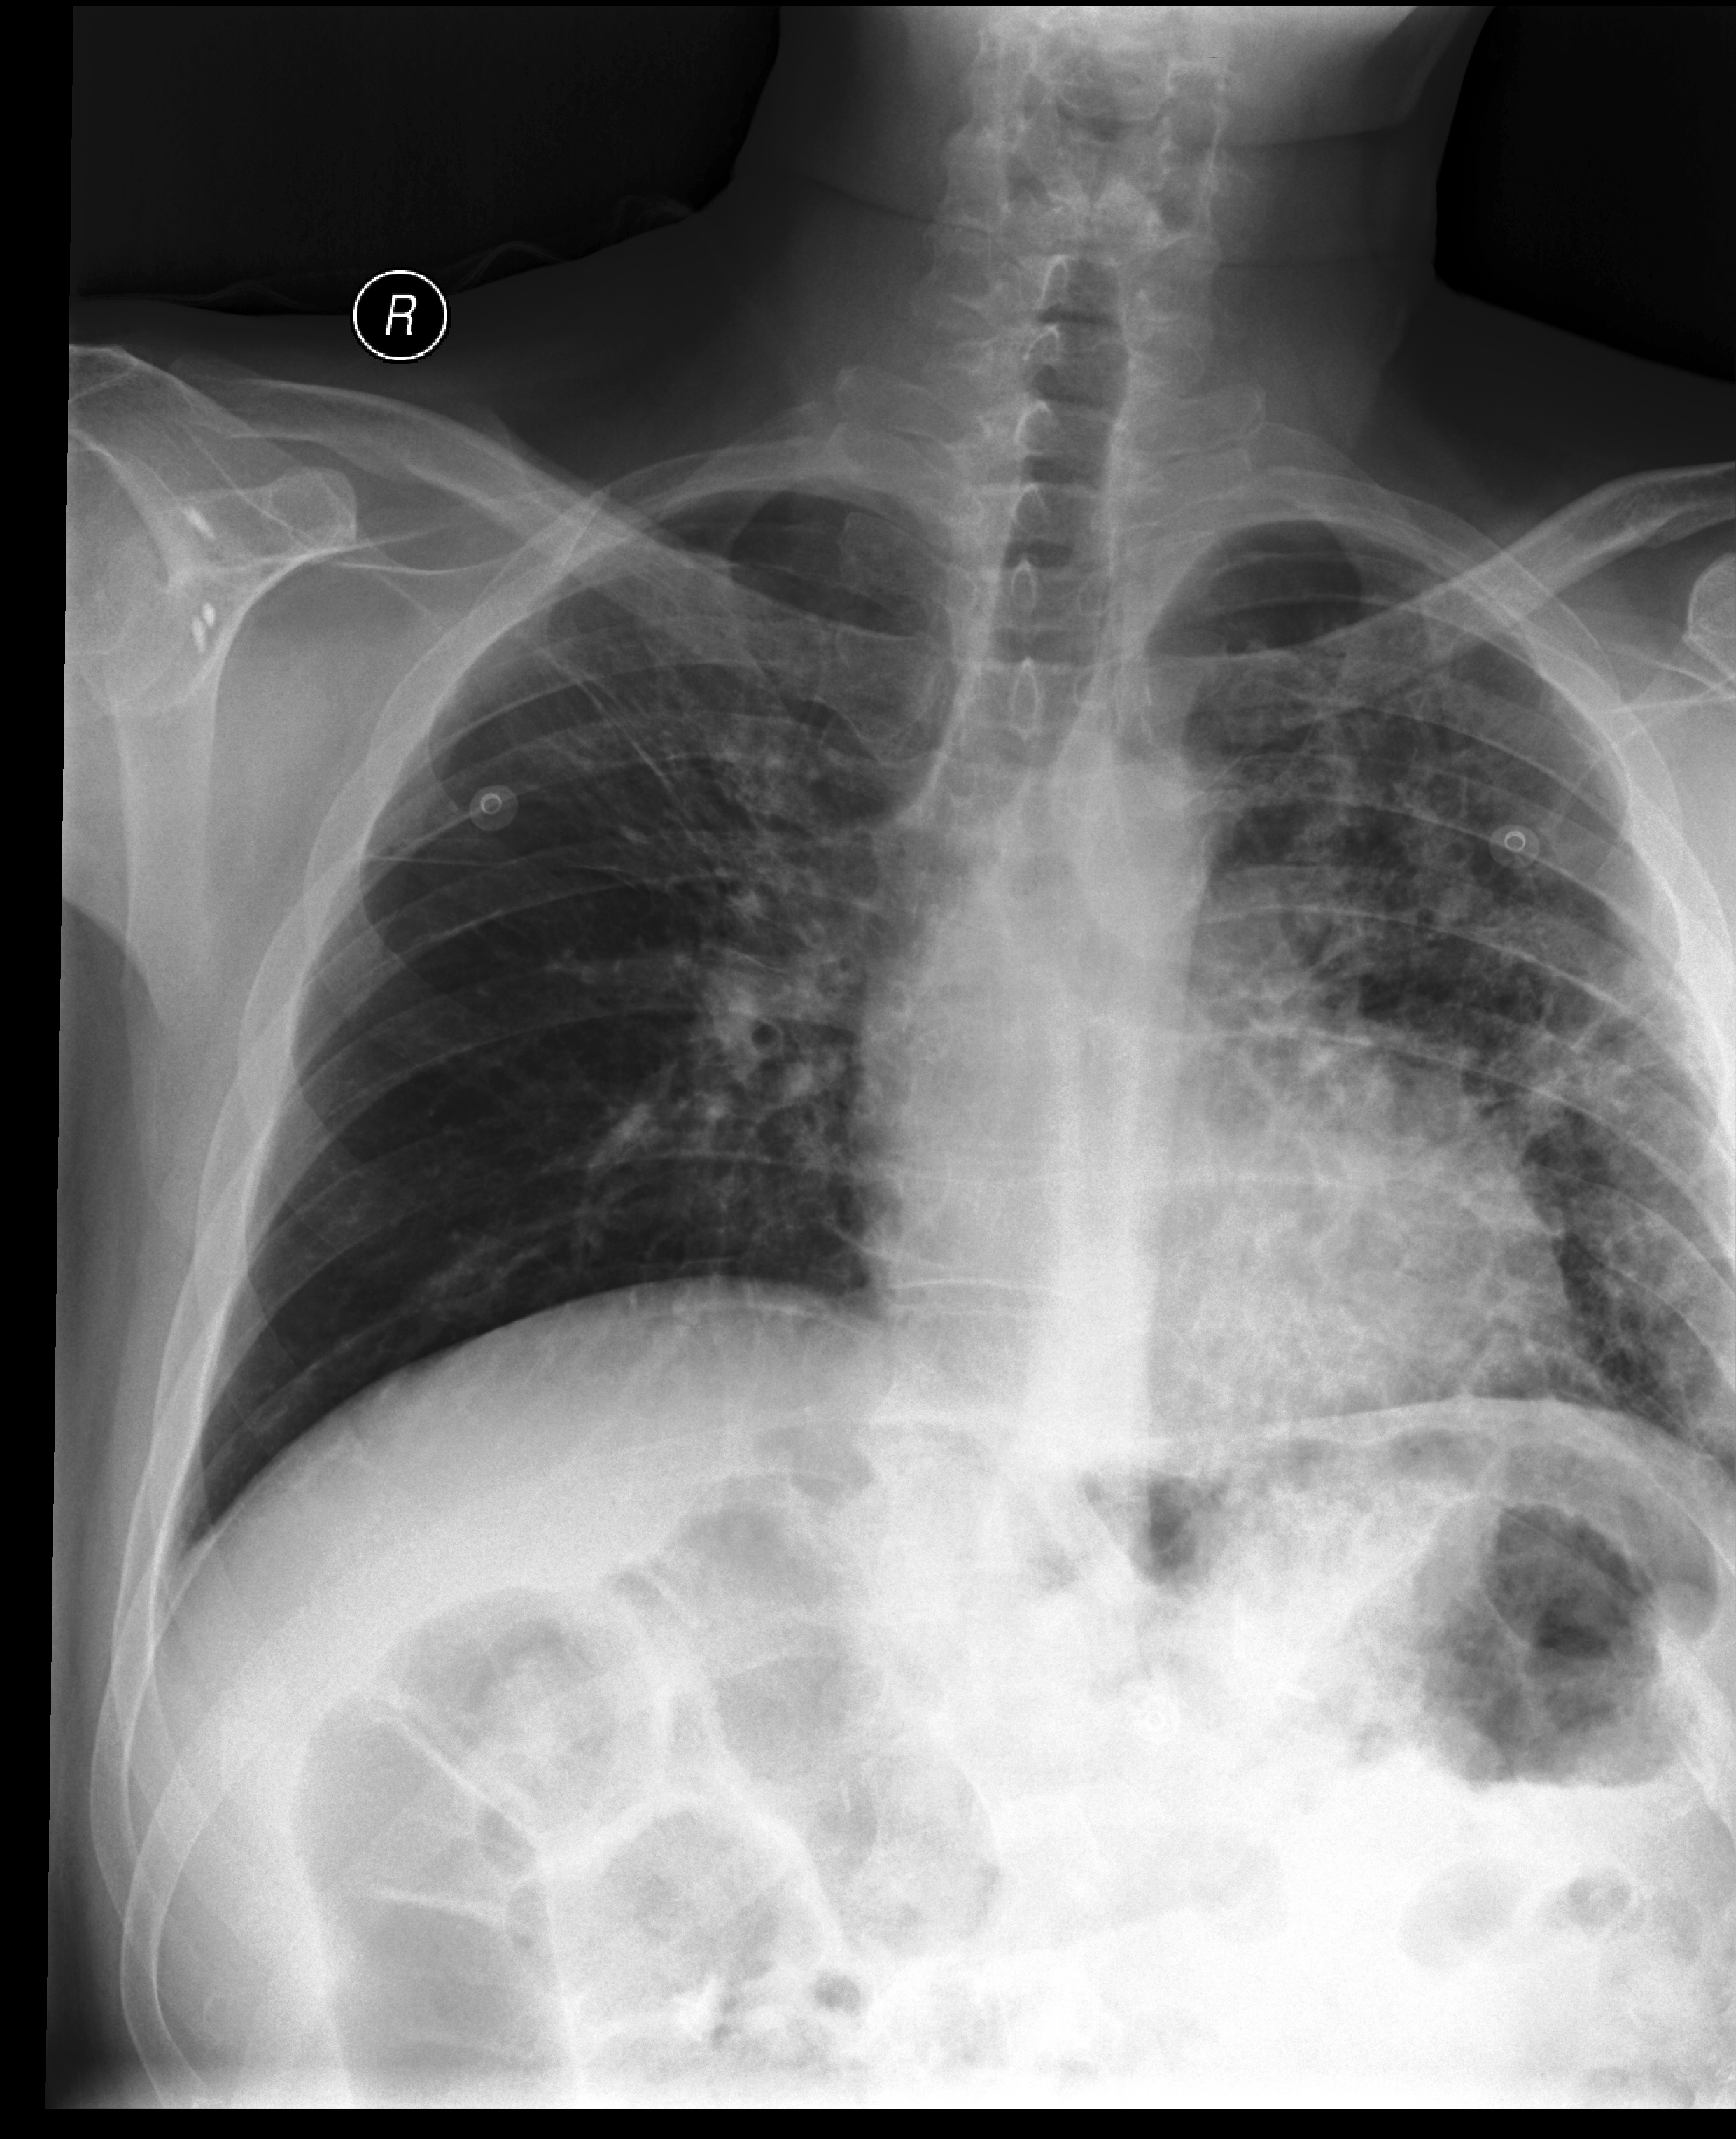

The results are shown in Table 2. Also, an example comparison of generated text from JRadiEvo and the ground truth on the test data is shown in Table 3.

| Example 1 | ||||||||

|

| Example 2 | ||||||||

| Example 3 | ||||||||